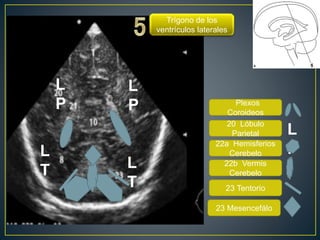

Plexos

Coroideos

20 Lóbulo

Parietal

22a Hemisferios

Cerebelo

22b Vermis

23 Tentorio

Trígono de los

ventrículos laterales

L

P

PL

T L

T

23 Mesencefálo